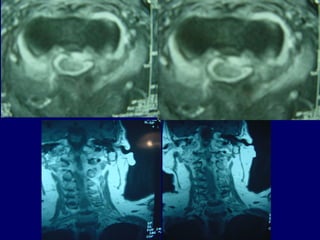

33rdrd

casecase

Ma. Pal.

F 56

Unknown origin

Symptoms

Neurologic deficit

Pain

Low fever

56

Follow upFollow up

Pus culture

(staphylococous aureous)

Antibiotics

i-v for 2 mts

orally for 6 mts

Complete neurologic recovery